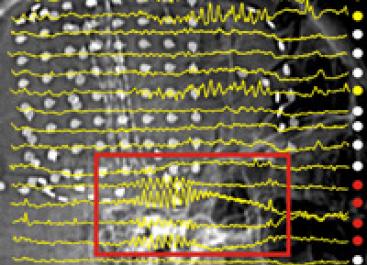

brain wave patterns

• In vivo electrophysiology (ECoG, EEG, depth electrode recordings)